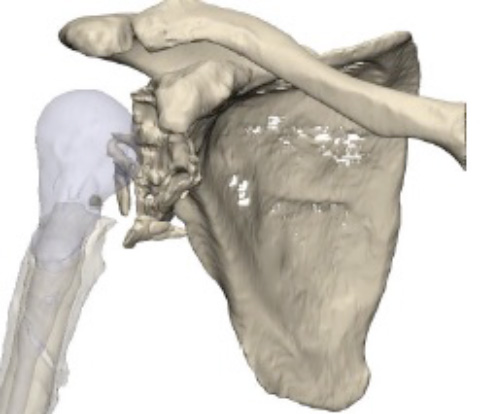

3D CT–Data analysis and resection proposal

- Resection of the inferior bone fragments on the glenoid side

- Cement removal from the humeral cavity

- First design proposal